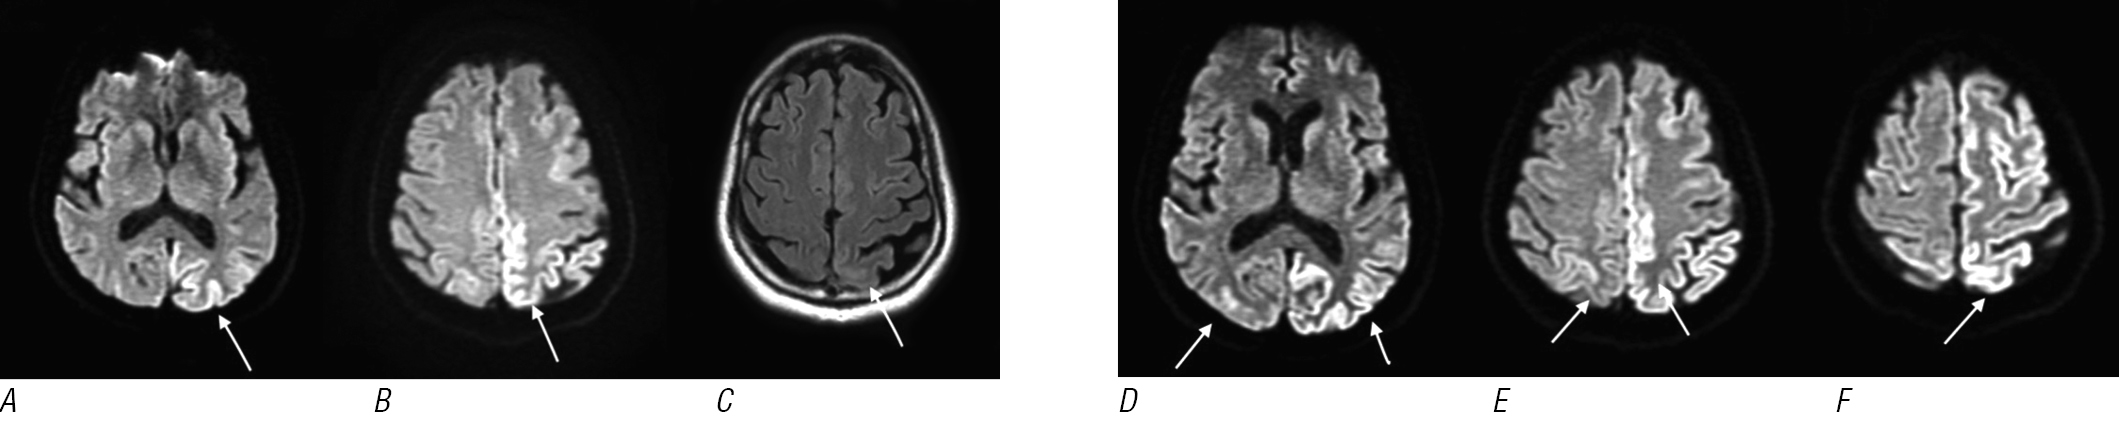

Результаты стандартных лабораторных тестов, включая общий анализ крови, оценку функции почек, печени, щитовидной железы, гликемию и электролиты, в норме. При магнитно-резонансной томографии (МРТ; рис. 1, A–C) головного мозга в режиме T2–FLAIR выявлены гиперинтенсивные гиральные очаги c соответствующим ограничением диффузии в режиме диффузионно-взвешенных изображений (ДВИ) в коре теменно-затылочной области левого полушария вдоль серпа. Признаков патологического накопления контраста не было. Изменений на МР-ангиографии нет. Гиральный паттерн поражения в сочетании с постепенным нарастанием симптомов позволил предположить наличие энцефалита. Анализ спинномозговой жидкости (СМЖ): клетки отсутствуют, уровень белка в норме. Тесты на наличие инфекций и иммунный ответ как в СМЖ, так и в сыворотке крови не выявили патологии. Учитывая недавно перенесённую пациентом лихорадку денге, рассматривалась вероятность постинфекционного энцефалита, и пациент получил пульс-терапию высокими дозами кортикостероидов.

Рис. 1. На ДВИ головного мозга в аксиальной проекции (A, B), полученных при первичном поступлении пациента, выявлено ограничение диффузии по гиральному типу преимущественно в левой теменной-затылочной области (стрелки).

С — очаги гиперинтенсивного сигнала в режиме T2–FLAIR в соответствующих областях; D–F — серия ДВИ головного мозга в аксиальной проекции, полученных при повторной МРТ при следующем поступлении пациента. Наблюдается усиление ограничения диффузии по гиральному типу с вовлечением контралатерального полушария и верхних отделов лобно-теменной области, перироландическая кора не поражена.

Состояние пациента продолжало ухудшаться, появились новые зрительные симптомы: макропсия и агнозия, а также усиление выраженности нарушений координации. У пациента стали отмечаться нарушения памяти, вплоть до невозможности вспомнить имя жены или сведения о своём образовании. При неврологическом обследовании когнитивный статус по МоСА составил 8/30, отмечалось существенное усиление выраженности брадикинезии и мозжечковых симптомов. Интервал между двумя тестами MoCA составил менее 3 нед. При повторной МРТ головного мозга выявлено увеличение выраженности ограничения диффузии в гиральных очагах в режиме ДВИ, соответствующих очагам гиперинтенсивного сигнала в режиме T2-FLAIR в височной доле обоих полушарий и в теменно-затылочной области левого полушария, за исключением перироландических областей; признаков патологического накопления контраста не было (рис. 1, D–F).